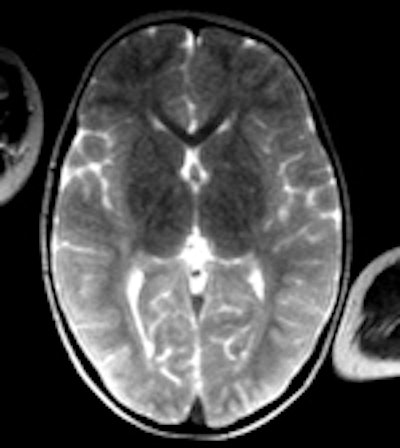

Ci-dessus: cet enfant a été retrouvé mort dans son lit; un scanner et un IRM post mortem ont été effectués un jour après l'heure du décès.

A gauche: scanner conventionnel, épaisseur de coupe de 5mm. A cause de la décomposition, il peut être difficile de différencier la matière grise et la substance blanche, même un jour après l'heure du décès. Au milieu: image 3D, rendu volumique. Cette technique permet dans certains cas de mieux maîtriser les changements post mortem dans l'atténuation cérébrale, mais il reste difficile de différencier les divers tissus cérébraux. Aucune pathologie n'a pu être détectée. A droite: l'IRM (séquence T2) offre une meilleure différentiation entre les divers tissus cérébraux. Si le corps a une température d'à peu près 10° C, les images IRM peuvent être assez bruyantes. Après le scanner et l'IRM, le syndrome de l'enfant battu a été exclu.Répondant aux questions des radiologues français, elle a expliqué que la technique pouvait être appliquée à des cadavres en état avancé de décomposition, du fait de la résistance surprenante des artères à la putréfaction. Son groupe a ainsi appliqué avec succès cette technique sur des cadavres au préalable gelés.